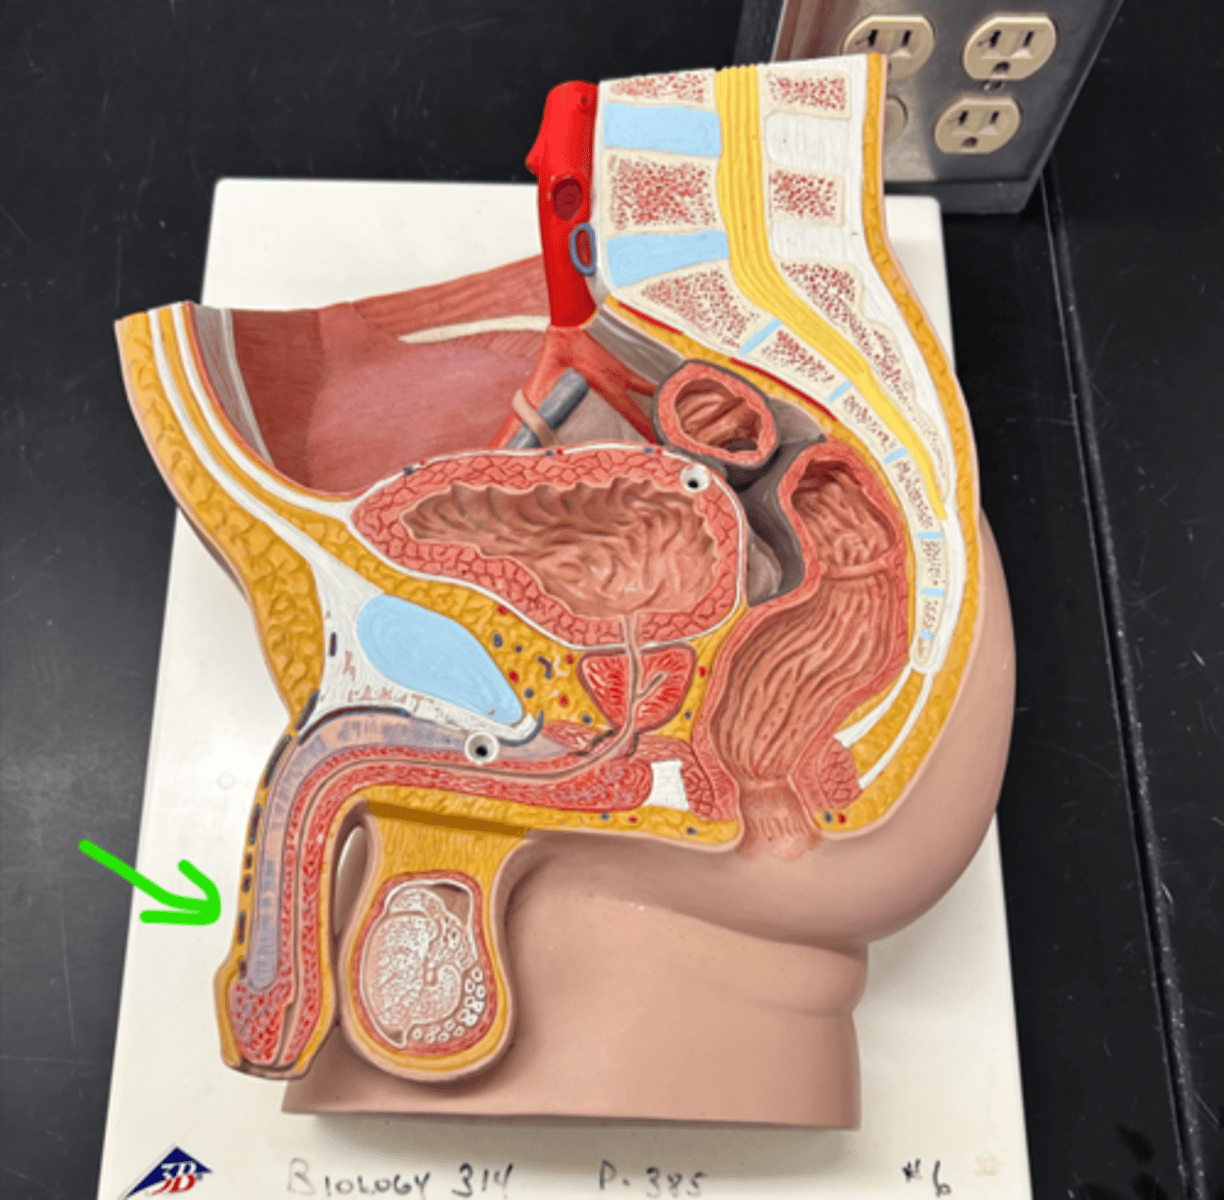

Chapter 30 Anat Phys: Male Reproductive System

Epididymis

Epididymis

Head (epididymis)

Epididymis

Epididymis

Body (epididymis)

Tail (epididymis)

Spermatic cord